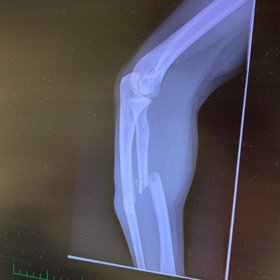

„Jsme v lese uprostřed ničeho a máme dvacet minut do příjezdu záchranky,“ natáčel své zranění Kazma (34), který měl namířeno na jednokolce do Tábora, kam však nedojel. „Viděl jsem, jak se mi ruka otočila na druhou stranu,“ komentoval svoje zranění.

V prvních minutách instastories to ale nevypadá vůbec dobře. Je poznat, že Kazmu zlomená ruka hodně bolí a nemůže se hýbat. Po celou dobu měl kolem sebe kamaráda, který zavolal záchranou službu a dokonce museli zasahovat i hasiči.

„Přijedou i hasiči,“ oznámil kolega Kazmovi ve videu po několika minutách. Chvíli poté dorazili na místo záchranáři, kteří Kazmovi ruku zafixovali a převezli ho do nemocnice. Nehodna nakonec nebyla tak vážná, jak to na první pohled vypadalo, ale na druhou stranu měl Kazma pořádné štěstí.